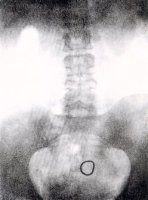

Balról: Eszköz a Gräfenberg gyűrü bevezetéséhez. A gyűrű 3 mintája. Rtgenkép a gyűrűről.